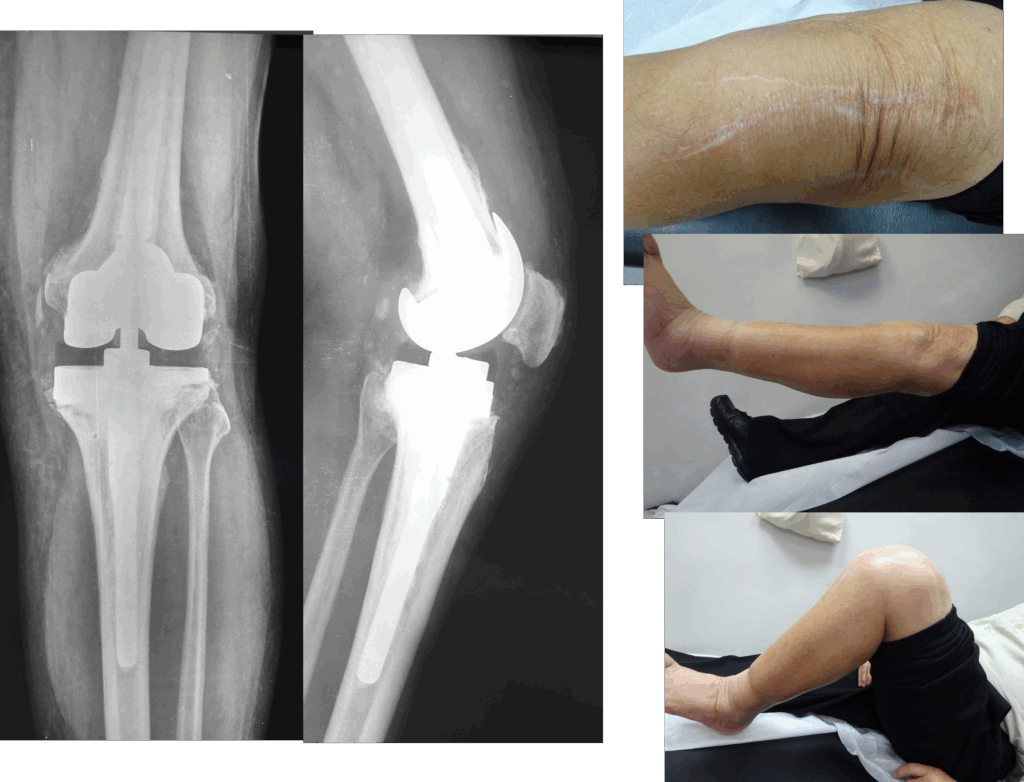

Η αναθεώρηση αρθροπλαστικής είναι μια δεύτερη χειρουργική επέμβαση που πραγματοποιείται όταν η αρχική πρόθεση (εμφύτευμα) του ισχίου ή του γόνατος έχει φθαρεί, χαλαρώσει, παρουσιάσει λοίμωξη ή αποτύχει για άλλους λόγους.

Η αναθεώρηση δεν είναι απλή αντικατάσταση, αλλά πιο σύνθετη επέμβαση που απαιτεί ιδιαίτερη εξειδίκευση και προσεκτική προετοιμασία.

Οι προθέσεις αναθεώρησης είναι πιο σταθερές, μακρύτερες και συχνά συνδυάζονται με μοσχεύματα ή μεταλλικά ενθέματα.